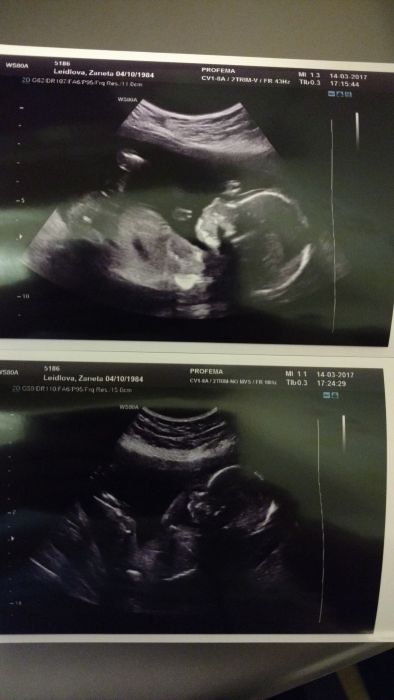

Ahoj holky, tak se hlásím po opravdu důkladné kontrole, takovou kontrolu jsem zažila opravdu poprvé, dr.měla super přístroj, kdy něco snímala a pak se k tomu zpětně vracela a ukládala do systému, viděla jsem průřez mozkem, 4 srdeční komory, aortu, oči, ústní patra...no toto by si měli pořídit v Podolí, úžasné..dr.zatím neshledala nic neobvyklého, opět mě upozornila, že výsledek je pouze na 90% a některé srdeční vady se můžou ještě ukázat až do 30tt..já už ani nevím jak to brát, vím, že to neovlivním, vím, že bych to měla brát, že to "zatím" vypadá dobře, ale my se s manželem prostě nechceme těšit a nevnímáme to úplně dobře. Tato dr.pracovala dřív v Motole, takže ty vyšetření co by mi udělali tam mi už udělala, ale já tam stejně raději půjdu. Objednala jsem se už i na 3D ult v 25tt a k tomu jsme objednali rodinné/těhu focení na červen, snad to vše výjde. Dostala jsem snad první krásnou nerozmazanou fotku, přikládám v příloze, pořád se musím na toho našeho klučíka koukat, i dcerka už se začíná těšit..snad to vše dobře dopadne..děkuji vám za podporu:-*